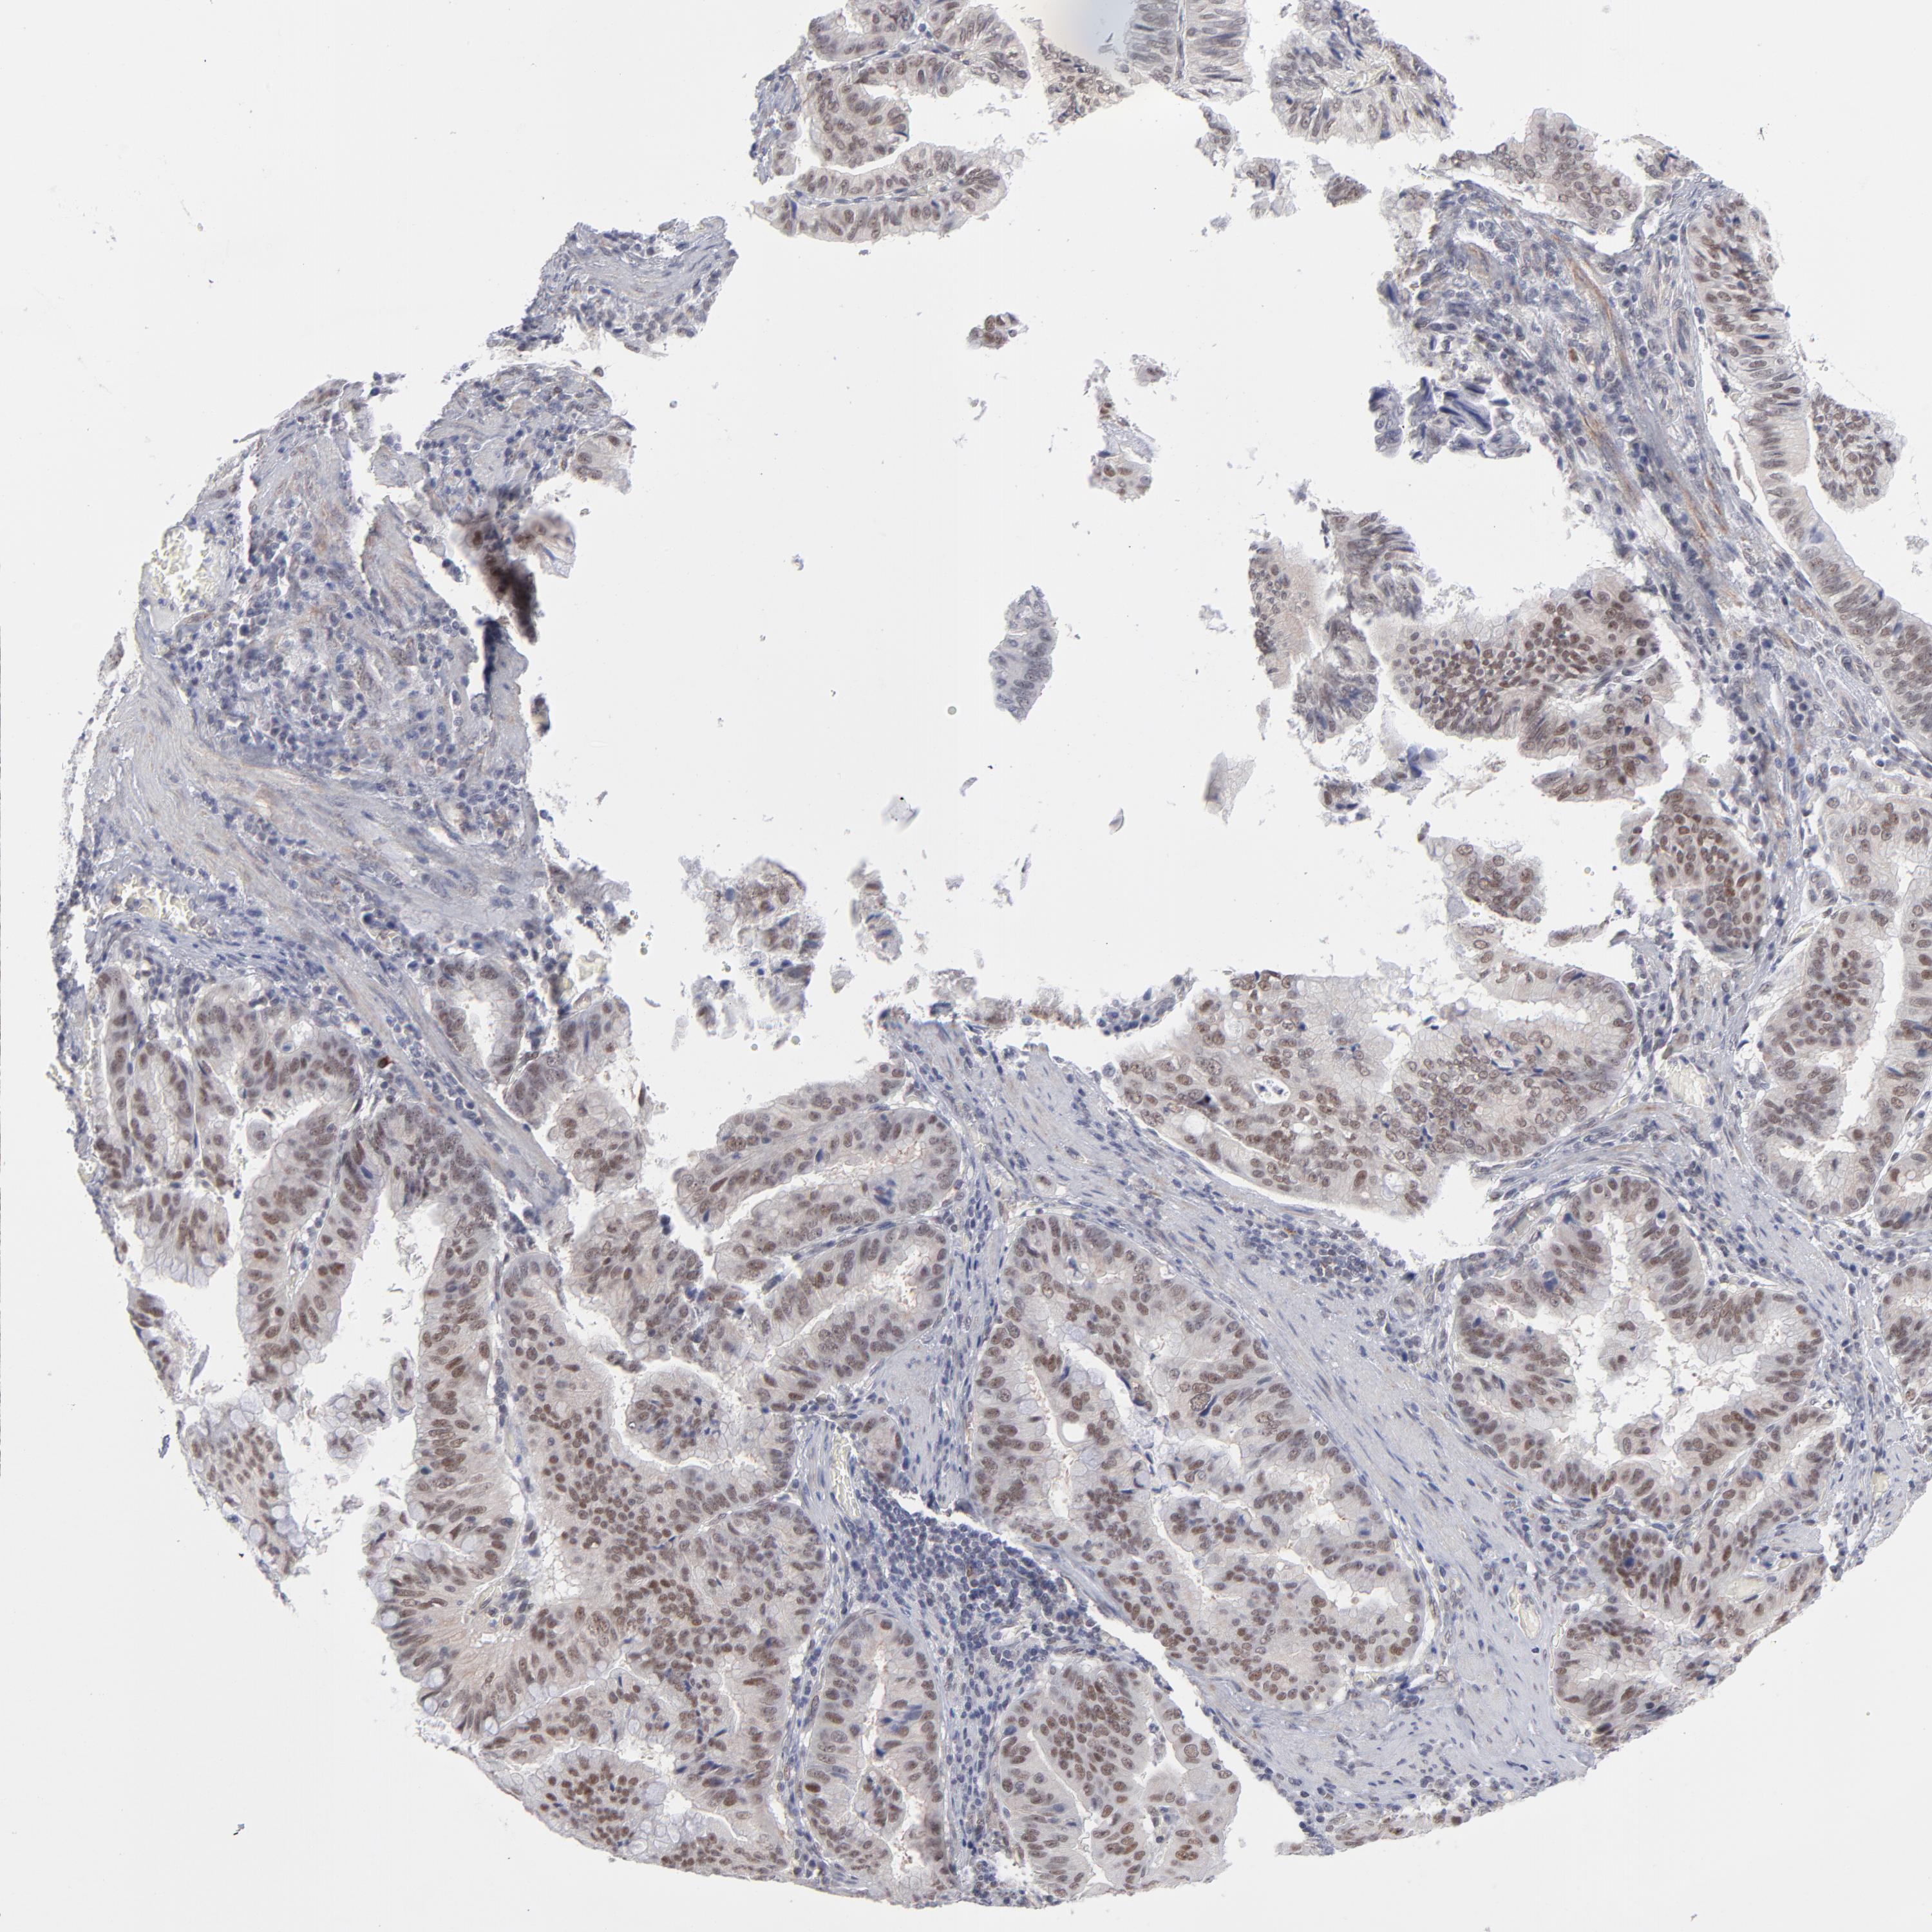

STOMACH CANCER - Protein expressioni

A mouse-over function shows sample information and annotation data. Click on an image to view it in a full screen mode. Samples can be filtered based on level of antibody staining by selecting one or several of the following categories: high, medium, low and not detected. The assay and annotation is described here.

Note that samples used for immunohistochemistry by the Human Protein Atlas do not correspond to samples in the TCGA dataset.

Antibody stainingi

Antibody staining in the annotated cell types in the current human tissue is reported as not detected, low, medium, or high, based on conventional immunohistochemistry profiling in selected tissues. This score is based on the combination of the staining intensity and fraction of stained cells.

Each image is clickable and will lead to virtual microscopy that enables deeper exploration of all samples and also displays staining intensity scores, fraction scores and subcellular localization as well as patient and tissue information for each sample.

Antibody HPA001429

Antibody CAB003836

Antibody CAB080233

Staining

High

Medium

Low

Not detected

Intensity

Strong

Moderate

Weak

Negative

Quantity

>75%

75%-25%

<25%

None

Location

Nuclear

Cytoplasmic/membranous

Cytoplasmic/membranous,nuclear

Adenocarcinoma, NOS

Adenocarcinoma, High grade